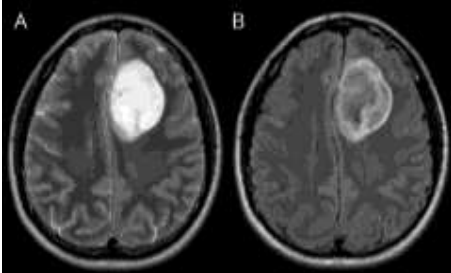

Durante a avaliação de uma ressonância magnética de um paciente com um tumor de origem glial recidivado (já diagnosticado por histopatologia), o radiologista se depara com o seguinte aspecto de imagem na avaliação das sequencias T2 e Flair.

Analise a importância do achado de imagem e assinale a alternativa correta.